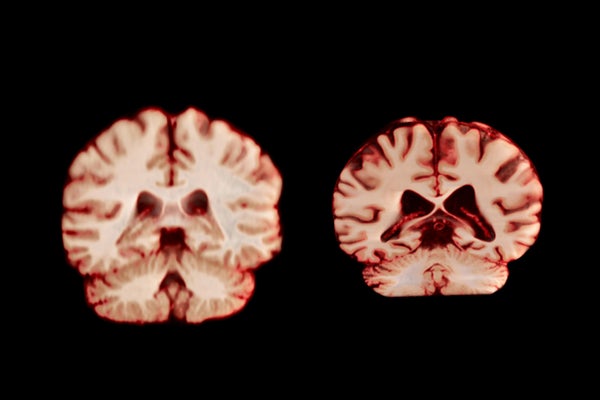

A healthy brain (left) and a brain affected by Alzheimer’s disease.

TheVisualMD/Science Source

During ageing, men experience a greater reduction in volume across more regions of the brain than women do, according to a longitudinal study published today in the Proceedings of the National Academy of Sciences. The authors suggest this means that age-related brain changes do not explain why women are more frequently diagnosed with Alzheimer’s disease than men are.

Overall, men experienced a greater reduction in volume across more regions of the brain than women did. For example, the postcentral cortex, which is responsible for processing sensations of touch, pain and temperature, as well as the body’s own position and movements, declined by 2.0% per year in men and by 1.2% annually in women.

If these changes did have a role in the development of Alzheimer’s disease, the study would have shown that women experience a greater decline in areas associated with the disease, such as the hippocampus and precuneus, which are involved in memory, says Amy Brodtmann, a clinician researcher in cognitive health at Monash University in Melbourne, Australia.